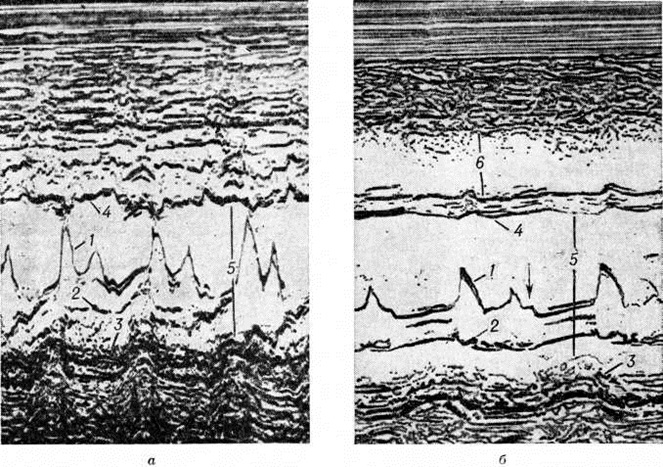

В заключительной стадии поражены обширные участки миокарда обоих желудочков, особенно — левого. В основном выявляются дистрофические и некротические изменения миокардиоцитов, начиная от вакуолизации перинуклеарной зоны цитоплазмы (смотри полный свод знаний Вакуолизация) и до цитолиза (рисунок 2) с полным растворением тел клеток (смотри полный свод знаний Цитолиз). От клеток остаются только следы в виде мелких зёрен липофусцина. В результате образуются ареактивные участки депаренхимизации миокарда (рисунок 3) с так называемой пустой сеткой, в дальнейшем замещаемые соединительной тканью. Ряд мышечных волокон подвергается мелкоглыбчатому и мелкозернистому распаду с образованием фуксинофильного детрита, резорбция которого также заканчивается миофиброзом. Процесс вакуолизации и лизиса распространяется и на клетки эндотелия кровеносных сосудов в очагах поражения. Процесс в целом напоминает дистрофический (деструктивный) миокардит. Нередко обнаруживаются также воспалительные лимфогистиоцитарные инфильтраты с примесью сегментоядерных лейкоцитов; в сочетании с дистрофическими изменениями создаётся картина смешанной формы идиопатического (аллергического) миокардита. Внутриорганные мелкие артерии и артериолы изменяются по типу аллергического васкулита (смотри полный свод знаний) — от фибриноидного некроза стенки (рисунок 4) до облитерирующего панваскулита. Все эти процессы обнаруживаются на фоне распространённых полей кардиосклероза различной зрелости (рисунок 5), подобно миокардитическому кардиосклерозу (смотри полный свод знаний Кардиосклероз), что свидетельствует о прогрессирующем и длительном течении поражения миокарда. В дистрофический и рубцовый процессы вовлечены и различные отделы проводящей системы с миоцитолизом (рисунок 6).